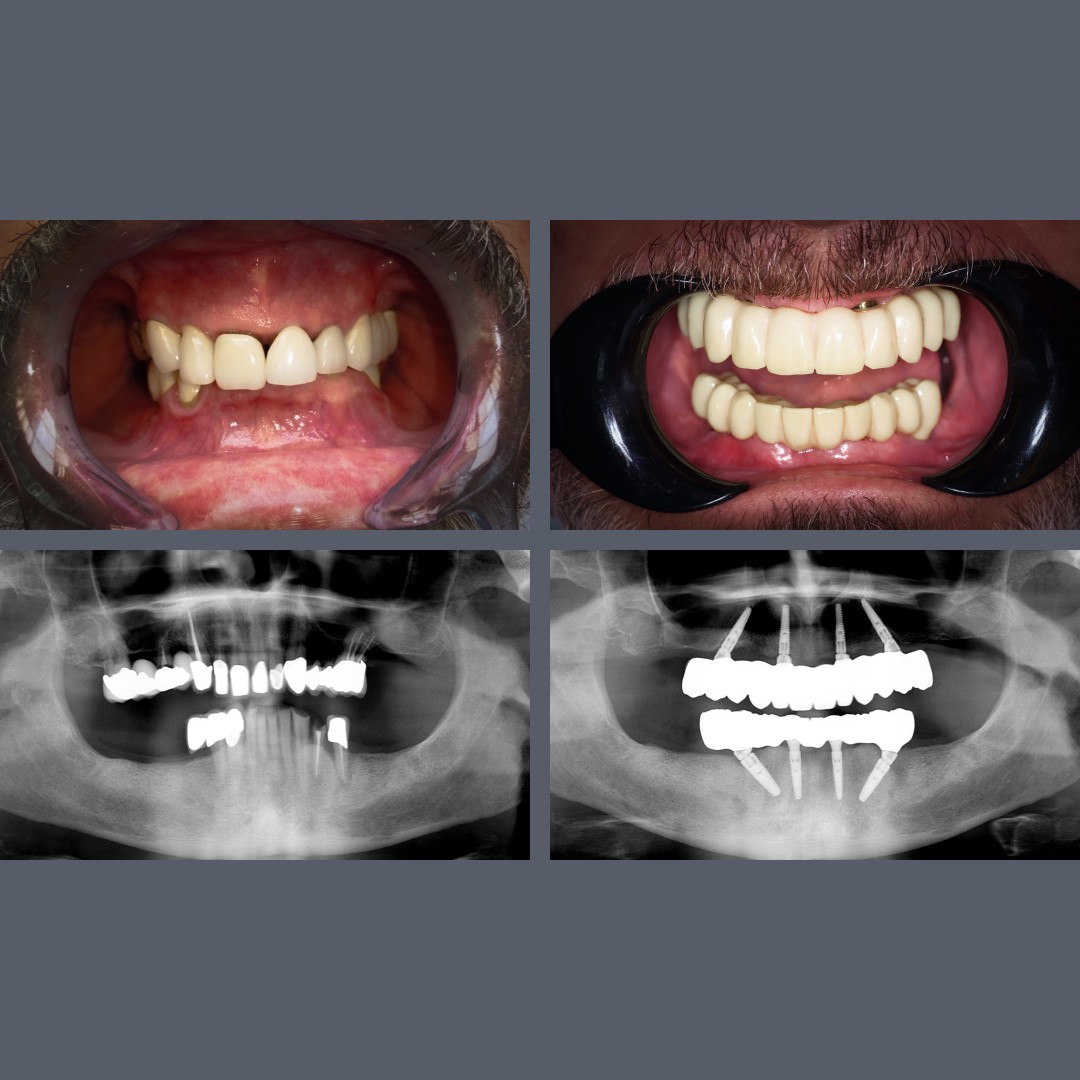

before-after

Full All-on-4® Rehabilitation: A Stable Bite and a Natural, Lifelike Smile

Treatment: ALL-ON-4®